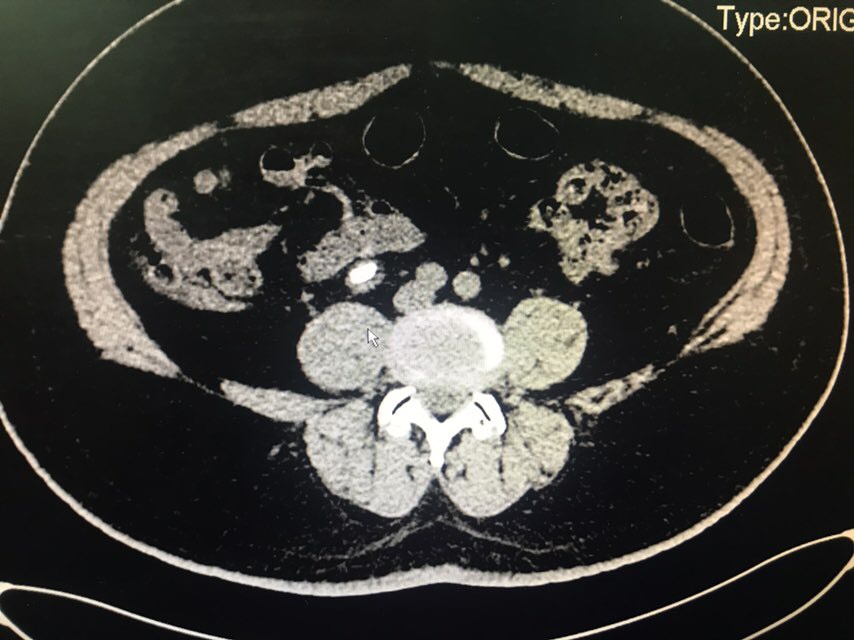

查体:无特殊。辅助检查:全腹CT(我院2018-8-6):右肾盂、肾盏及右输尿管上段明显扩张、积水;右侧输尿管置管。左肾盏区点状结石;双肾囊肿可能。膀胱充盈,壁稍增厚、毛糙,合并炎症可能,胆囊结石。脂肪肝;肝右叶小钙化灶。

从患者CT片子上看,患者右侧输尿管下段狭窄,输尿管支架管返折,因膀胱镜下未能成功取出,故行右侧输尿管探查术。手术顺利,术后给予曲克芦丁脑蛋白水解物注射液5ml治疗,患者术后恢复良好。